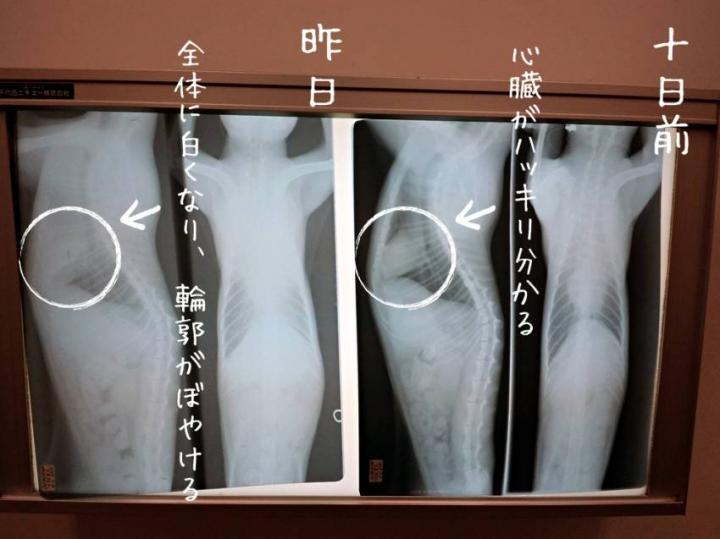

キムンの呼吸がやや荒くなり、

病院に駆け込んでレントゲンを撮影していただきました。

10日ほど前に撮影したものと、

昨日のものを見比べると、

胸水が再び溜まってきていたことが確認できました。

↑先日のものでは心臓の境界線が見えにくくなっていました